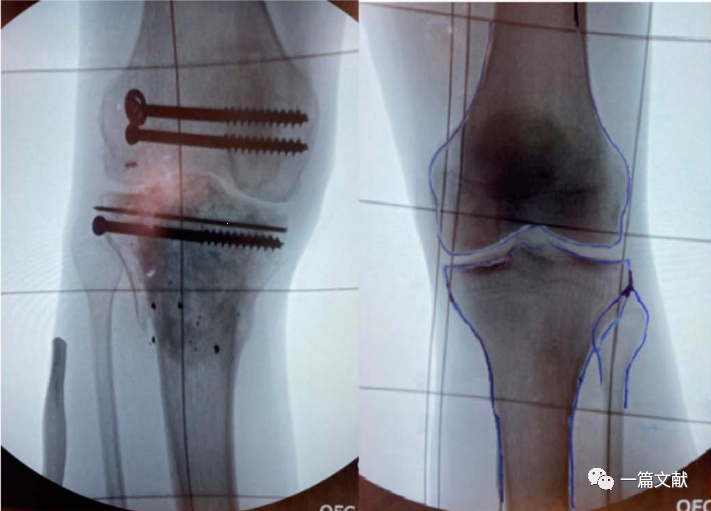

3、胫骨平台手术

对于累及双侧髁骨折,近端移位明显的骨折尤其有用,如下图: